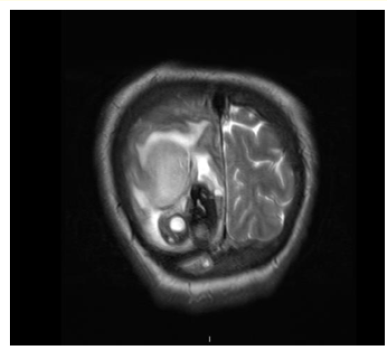

Holoprosencephaly Alobar: Contribution of Cerebral CT Scan in a Case Report

Khadija Laasri, Siham EL Haddad, Manal Jidal, Nazik Allali and Latifa Chat. 15(5): 53-56.